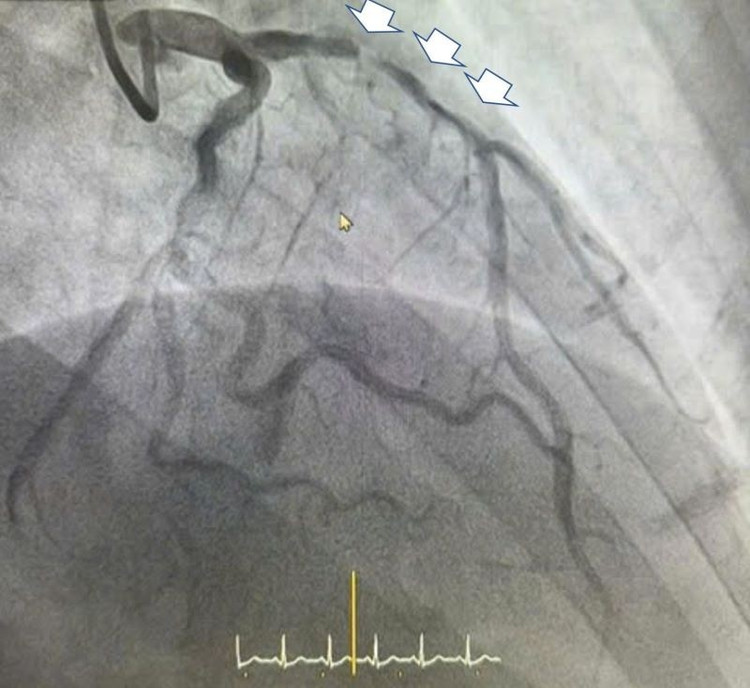

Tổn thương hẹp rất nặng - Ảnh BVCC

Kết quả chụp cho thấy bệnh nhân bị hẹp rất nặng động mạch liên thất trước và hẹp 80-90% động mạch vành phải, nguy cơ diễn tiến rất xấu nếu không được can thiệp kịp thời. Ngay lập tức, bệnh nhân được chỉ định đặt stent động mạch liên thất trước để tránh biến chứng nguy hiểm của nhồi máu cơ tim cấp.

BSCKII.BSNT Lê Đức Hiệp, khoa Tim mạch - Tim mạch can thiệp Bệnh viện Đa khoa Hồng Ngọc Phúc Trường Minh, cũng là người trực tiếp cùng ê kíp thực hiện ca can thiệp đặt stent cho anh H. cho biết: Động mạch liên thất trước của bệnh nhân bị hẹp rất nặng, nếu không can thiệp ngay có thể bệnh nhân sẽ đối diện với các biến cố thường gặp do nhồi máu cơ tim như suy tim nặng dẫn tới sốc tim, rối loạn nhịp thất nguy hiểm đe dọa trực tiếp đến tính mạng.